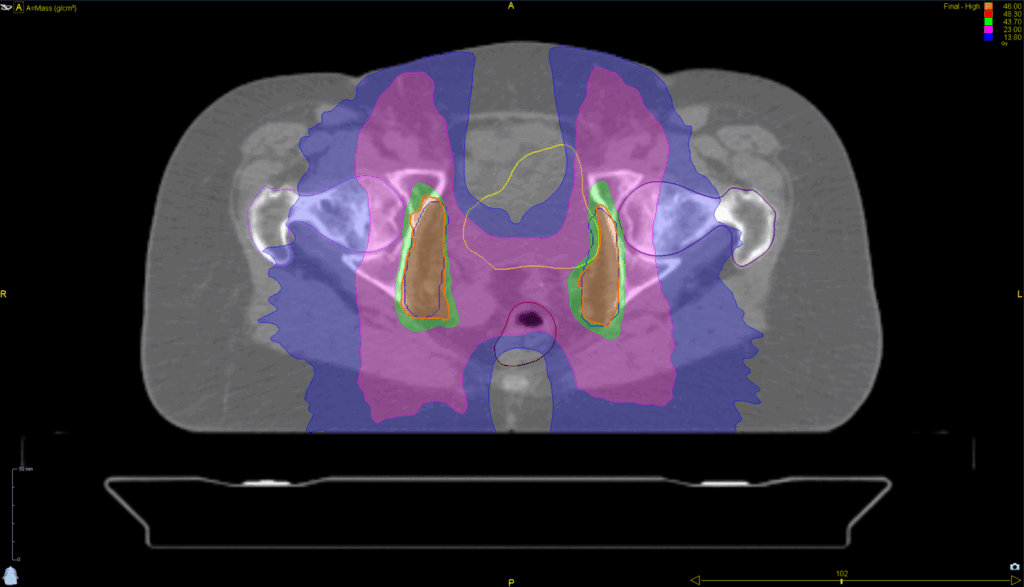

Treatment Plan Images

Fractionation / Protocol Used

46 Gy in 23 fractions